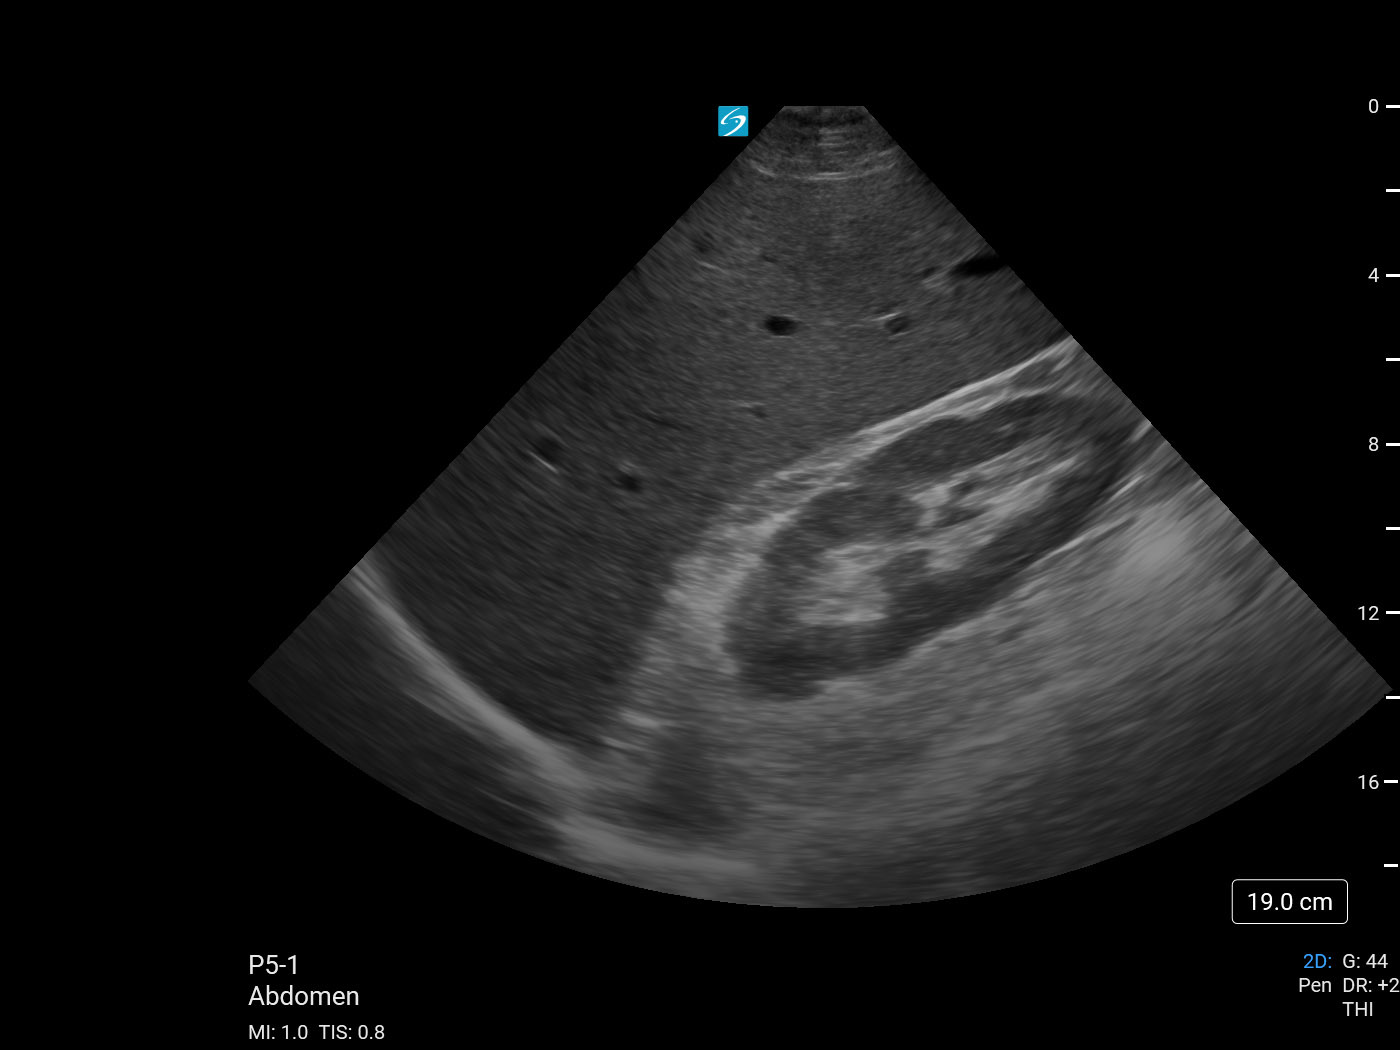

eFAST/RUSH 右上腹 (RUQ) 肝脏/右肾 1 图像